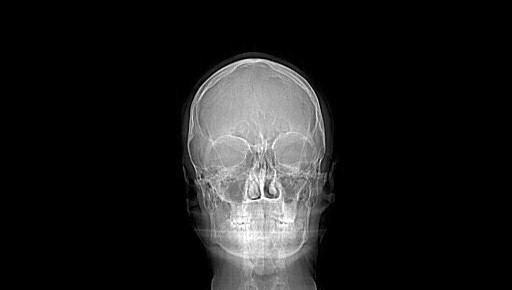

Buongiorno, è da anni che soffro di click mandibolare nella parte destra in apertura ed in chiusura, ho incontrato diversi specialisti che mi hanno diagnosticato un morso profondo e prescritto diversi bite che di fatto non hanno risolto nulla. Sono stato di recente anche da un chirurgo maxillo facciale il quale mi ha proposto un intervento di artroscopia dell'atm e sinceramente quest'ultima ipotesi vorrei davvero evitarla perchè si tratta di un intervento in anestesia generale. Il referto della tac del massiccio parla di "una modesta riduzione di ampiezza dello spazio intraarticolare con appiattimento della porzione apicale del condilo da ambo i lati". Secondo voi è davvero una soluzione valida l'artroscopia? Non è davvero possibile evitarla con una terapia tramite bite ed ortodontica? Allego tc massicio 3d. Vi ringrazio

Sig. Francesco, qui manca tutto, non c'è nemmeno un tracciato cefalometrico di diagnosi scheletrica, per cui è impossibile dirle se è indicato un intervento i artroscopia.